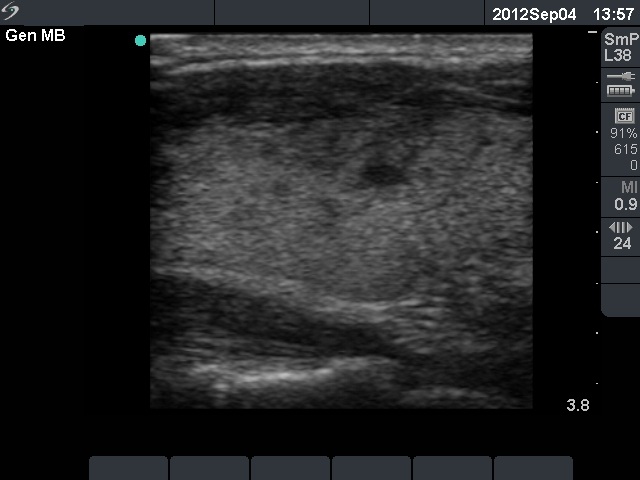

Follow-up examination 3 weeks later (3rd row of images):

Ultrasonography: a relatively large hypoechogenic lesion with decreased vascularization has evolved in the previously intact right lobe. On the other hand, the hypoechogenic area in the left lobe significantly decreased in size and the vascularization normalized.